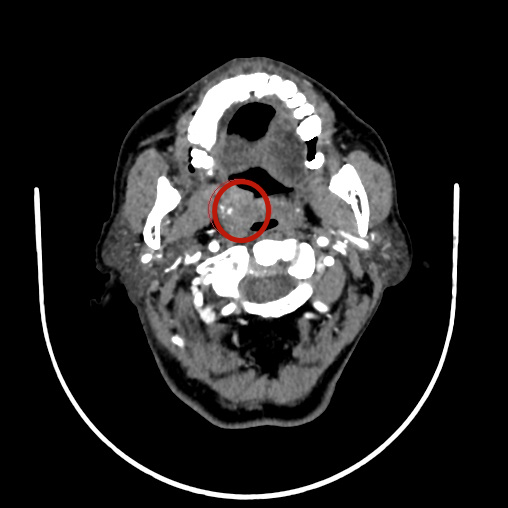

经过影像学检查,王爷爷腭部的肿瘤范围明确初步诊断为:软腭恶性肿瘤(鳞癌)

刘蓉蓉主任介绍道:「我们发现肿瘤侵犯了软腭全层,为了防止肿瘤复发,需要做扩大范围的切除。由于切除范围比较大,切除以后的创面修补会比较困难。幸运的是,目前肿瘤还局限在软腭范围内,没有侵犯硬腭,颈部淋巴结也没有发现有转移迹象。」

术中发现如刘主任术前评估的一致,王爷爷的软腭肿瘤不但侵犯了全层,而且范围比较大。肿瘤切除后,形成了直径约 2 cm 的腭部穿孔,加之口腔内操作空间极其狭窄,修补起来困难很大。刘主任运用扎实精湛的外科技术,对腭部穿孔进行了修补。